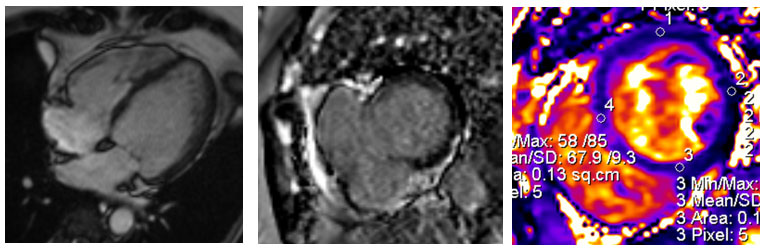

Arrhythmogenic Cardiomyopathy in a Young Athlete

In a cardiac MRI of a 20-year-old volleyball/basketball player with a family history of heart disease, the right side of the heart was enlarged and weak, with poor pumping function. Six months later, follow-up scans showed early scarring of the heart muscle. Although she had no symptoms at first, she later developed ventricular arrhythmia, a heart rhythm problem. She eventually required a defibrillator device to restore a normal heartbeat, and later a heart transplant.